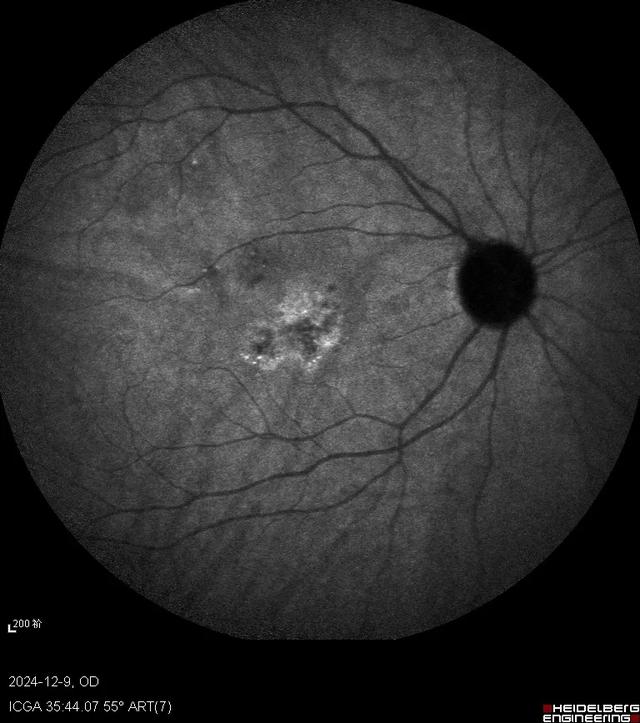

马上对此患者进行了抽血检查来判断是否存在梅毒感染,另外还安排了眼底荧光素血管造影(FFA)和吲哚菁绿(ICG)造影检查。因为我们知道梅毒是“模仿大师”,可以引起视神经炎、视网膜血管炎、脉络膜炎等多种眼底改变。很快造影结果就出来了,右眼FFA黄斑早期高荧光,晚期高荧光衰减;而ICG则早期低荧光,晚期高荧光;左眼FFA黄斑渗漏较右眼明显,ICG晚期也是表现为高荧光。双眼自发荧光类似,表现为中央低荧光,围绕一圈周围高荧光。果不其然,符合这时候梅毒性后极部鳞状脉络膜视网膜炎的临床表现。

ICG右眼

ICG左眼

关于梅毒性后极部鳞状脉络膜视网膜炎,《中华眼科杂志》有一篇彭晓燕教授的文章,总结的很好,我引用一下1。彭老师的这组患者共10人,其中8人为双眼发病。视力介于指数~0.8,中位数0.3。仅1例患者出现前房炎症反应。眼底病变均集中在以黄斑为中心的后极部。6只眼表现为鳞样病灶,4只眼表现为弥漫黄白色病灶,其余是混合型。OCT提示主要累及外层视网膜,显著特征是椭圆体层部分或全部消失,RPE结节,玻璃体内细胞。自发荧光表现为斑片状或弥漫高荧光。FFA静脉后期开始轻度高荧光,晚期渗漏。ICGA中晚期低荧光,夹杂针尖状高荧光点。在文献的引导下,我重新回顾了一下OCT,当我把扫描线拉到黄斑区外时,确实发现了很多玻璃体细胞,所以看OCT时还需要更仔细一些。

梅毒性后极部鳞状脉络膜视网膜炎的临床特征包括青壮年、急性双眼起病、视力下降显著而眼部体征较轻。OCT上黄斑区椭圆体带不同程度损伤伴有RPE结节和玻璃体细胞。自发荧光、FFA、ICG、眼底彩照表现为后极部累及黄斑区鳞片状或弥漫性病灶。在临床分析中,要抓住点点滴滴的蛛丝马迹,往往一些容易被忽略的小问题最后会成为“破案”的钥匙,借此病例,与眼科同道们共勉!